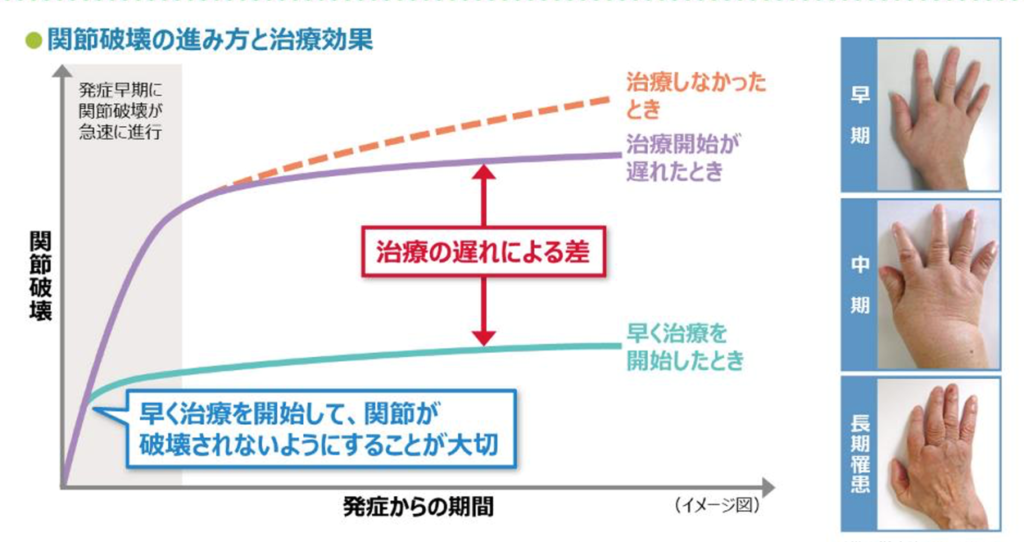

早期治療がカギ

重要なのは「早く見つけて、早く治療する」ことです。

関節リウマチは、発症から早い段階で治療を開始すると関節破壊を防ぎやすく、長期的な予後が大きく変わります。逆に、長く放置すると炎症が続き、関節の変形や機能障害が進んでしまうことがあります。

現在は血液検査や画像検査の進歩により、比較的早期から診断できるようになってきました。

そのため、「関節が痛いけど年齢のせいかな」と我慢せず、早めに医療機関を受診することがとても大切です。